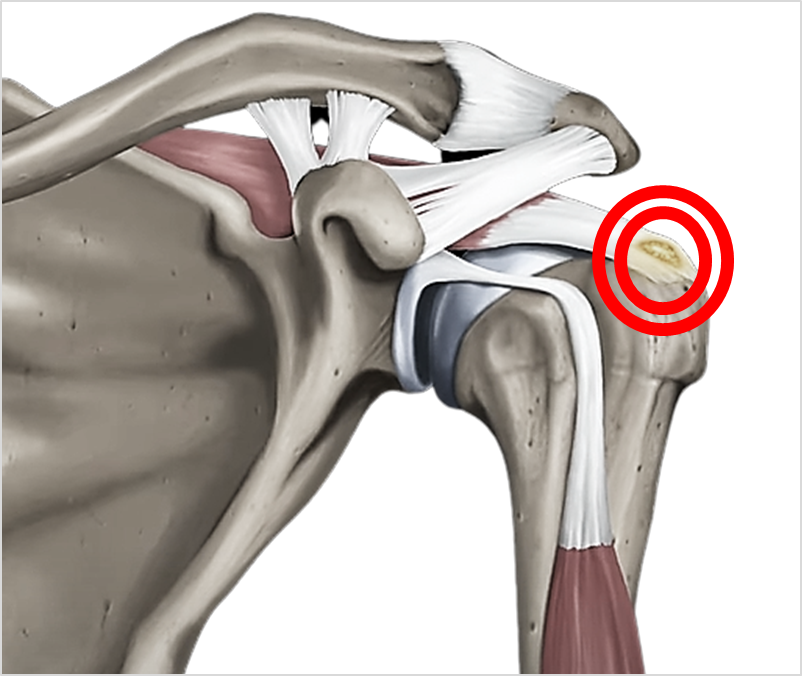

◈ 석회성건염이란?

어깨 힘줄의 퇴행성 변화 등에 의해 석회가 생겨나 염증이 발생하고 심한 통증이 생기는 질병이다. 시기에 따라 석회는 딱딱하거나 치약과 같은 무른 형태일 수 있다.

◈ 석회성건염의 원인은?

하지만 가장 유력한 가설 중에는 혈액공급이 원활하지 못해 생기는 것으로 보고 있다. 퇴행성 파열이나 혈관의 문제로 혈액공급이 줄어드어 국소적으로 산소가 보족한 부위에 석회가 침착된다는 가설이 유력하다.